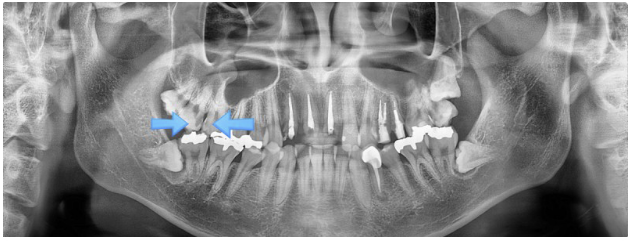

이 사례에서는, 가장 뒤쪽에 부러진 사랑니는 발치를 진행하였고, 앞쪽 화살표로 표시된 두 개 치아는 신경치료를 시행하게 되었습니다.

반면 오른쪽 치아는 신경치료를 통해 치료를 마무리하였습니다.

이 사례에서 알 수 있듯, 같은 통증을 경험하더라도 충치의 깊이와 진행 정도에 따라 치료 방법과 결과가 달라질 수 있습니다.